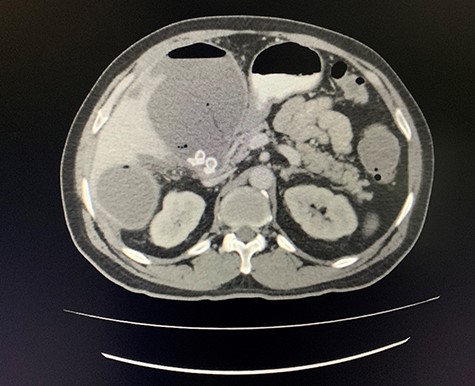

A size 12 French percutaneous catheter was inserted into the large liver abscess. The purulent material drained tested negative for organisms, amoebic and hydatid disease (Fig. 4). A sinogram was performed by injecting contrast through the catheter, showing passage into the ascending colon, confirming the initial diagnosis (Fig. 5).

Axial view of arterial phase of CT scan of the abdomen cholecystitis with pneumobilia with resolving liver abscesses with percutaneous pigtail catheter in situ.